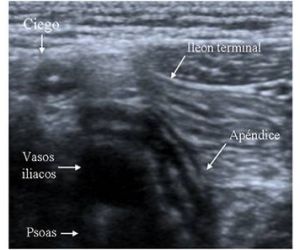

Ecografia Apendicular.

La apendicitis se produce como consecuencia de la obstrucción de su luz, es decir, del conducto interno del apéndice. Esta obstrucción sucede por diferentes motivos: Hiperplasia de folículos linfoides: es la causa de apendicitis más frecuente.

El microorganismo que más se relaciona con la apendicitis es la Yersinia.

- Dolor repentino que comienza en el lado derecho de la parte inferior del abdomen.

- Dolor repentino que comienza alrededor del ombligo y, a menudo, se desplaza hacia la parte inferior derecha del abdomen.